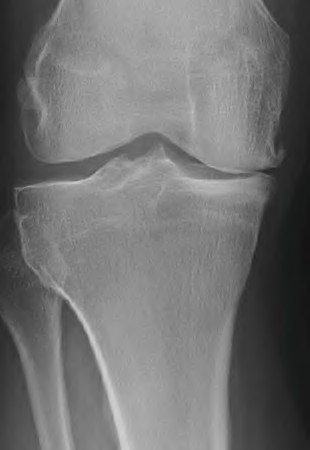

The radiograph seen in Figure A reveals varus alignment of the knee, with medial tibial deficiency; from this X-ray the patient appears to have unicompartmental arthritis. Treatment options for unicompartmental arthritis include high tibial osteotomy, interpositional arthroplasty, unicondylar knee replacement and total knee replacement. Interpositional arthroplasty became popular in the 1950’s when early outcomes analysis seemed to indicate good results; long term follow up in one study found 0/12 excellent results, with all patients requiring conversion to TKA. This procedure is no longer recommended due to the poor long term outcomes.

While an osteotomy is still used for young and active patients, unicompartmental or total knee arthroplasty have largely replaced this treatment in older patients. Advantages of UKA and TKA include more predictable relief of pain, quicker recovery, and better long-term results. Criteria for UKA include limited unicompartmental disease, no more than a fixed 10 degrees of varus or 5 degrees of valgus deformity from neutral and an intact anterior cruciate ligament with no signs of medial lateral subluxation of the femur on the tibia; this patient is therefore not a good candidate for this procedure.

Total knee arthroplasty can be used to provide predictable pain relief in a patient with unicompartmental and tricompartmental degenerative disease and varus malformation of the knee and for this patient is the best option.